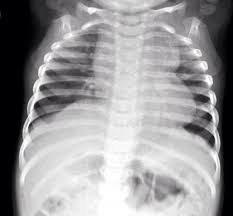

CXR: 장화 모양 심장(Boot-shaped heart)